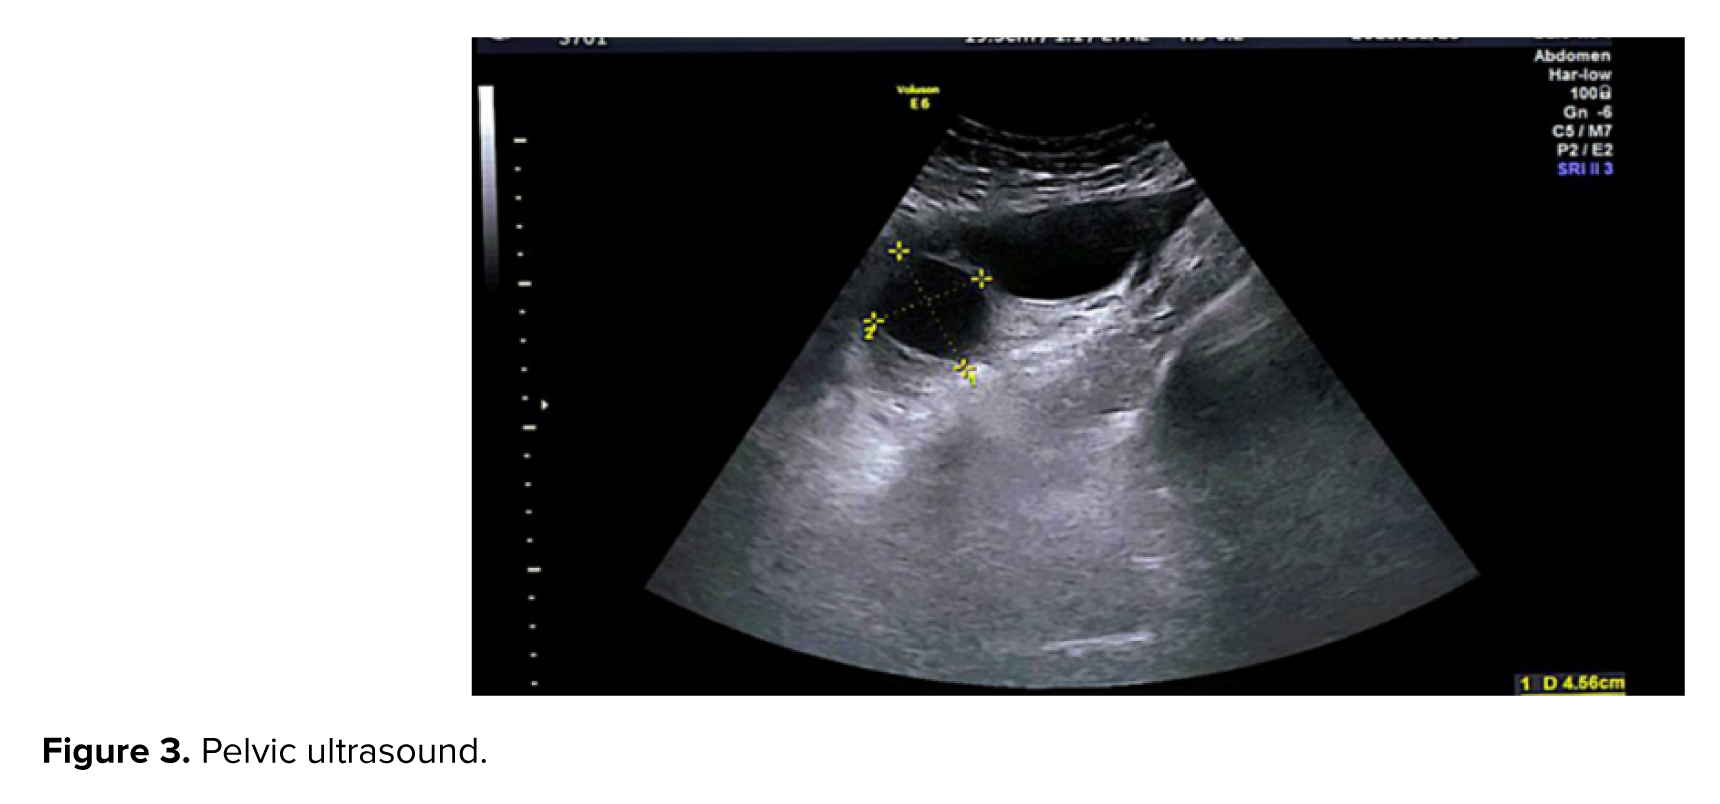

4 wk later, the case presented with complaints of severe vaginal bleeding and increased β-hCG titer (31037) after suction. Upon admission to the emergency department, vital signs were as follows: blood pressure, 110/75 mmHg; pulse, 84 bpm; temperature, 36.5°C; and respiratory rate, 18 breaths/min. Abdominal and pelvic examinations were normal. A pelvic ultrasound was performed. The ultrasound results showed heterogeneous remnants (63 and 50 mm) in the uterine cavity and 3 cysts (51 and 37, 48 and 51, and 27 and 45 mm) in the left ovary and 3 cysts (59 and 56, 60 & 53, 48 & 40) in the right ovary and some free fluid in the pelvic cavity (Figure 3).